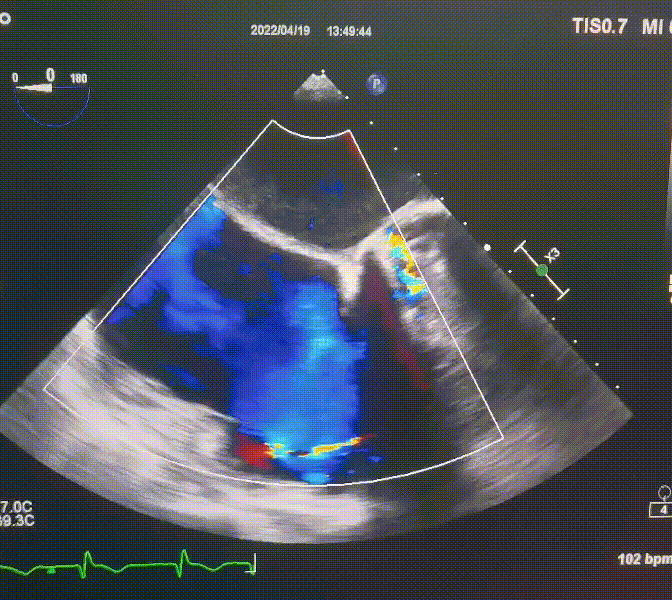

此次手术在全麻下进行,采用经右侧颈静脉入路。术中在经食道超声和DSA的指引下多个维度精细调整输送器角度,在达到正确位置后,逐步释放瓣膜锚定装置和盘片,最终完成瓣膜植入。术后患者右房压明显下降,术后超声提示人工三尖瓣同轴性良好,瓣架固定牢靠,无反流和瓣周漏,血压术后即刻上升20mmHg左右,手术后监护室顺利拔除气管插管,3天后恢复良好,予以出院。

图2.术后超声